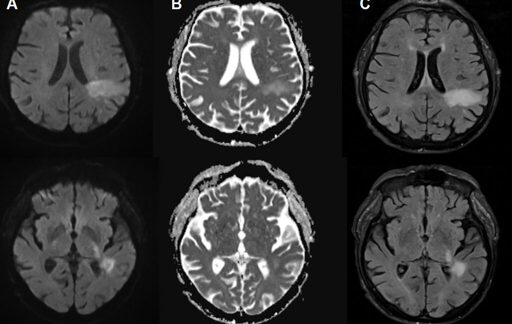

The virus is the human polyomavirus 2, commonly called either the JC virus or John Cunningham virus, named after the poor patient from whom it was first isolated in 1971. It shows up in the urine and stool of infected people and spreads via the fecal-oral route. Many people are thought to be infected early in life, and blood testing surveys have suggested that 50–90 percent of adults have been exposed at some